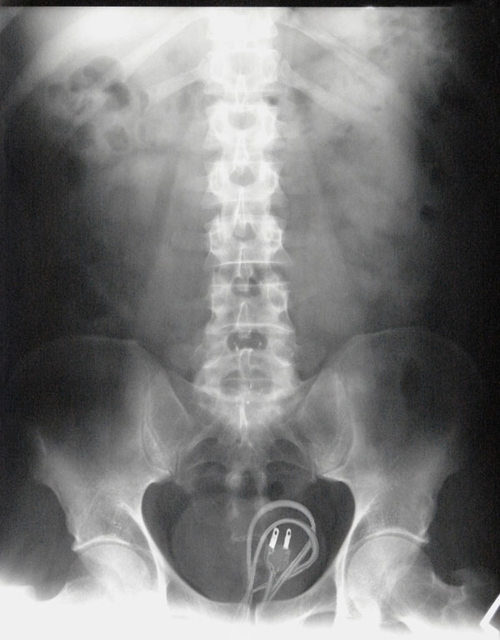

3. This gives a whole new meaning to the term “butt plug.” (I had to.)

8. People sure do like sticking stuff that doesn’t belong there up their butts.